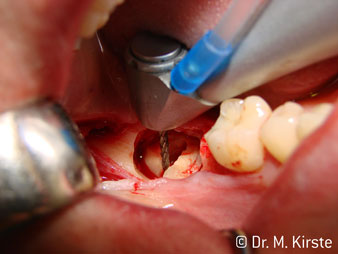

Die Winkelwahl des 45° Handstücks bringt viele Vorteile in der Anwendung. Chirurgisch tätige Kollegen, und für diese ist das Handstück in erster Linie entwickelt worden, werden schnell bemerken, dass man sehr gezielt arbeiten kann. Insbesondere bei der Weisheitszahnentfernung (Abb. 2) bedarf es keiner großen Weichteilabspreizungen im Wangenbereich (Abb. 3). Die Handstückkopfgestaltung kombiniert mit leichten Kopfdrehungen bei der Präparation lassen ein sicheres und schnelles Arbeiten im retromolaren Bereich zu.

Apropos schnelles Arbeiten: Es können über 100.000 U/min erreicht werden. Eine absolut professionelle Kühlung und ein kleiner Ansatzkopf lassen keine Fragen hinsichtlich thermischer Effekte oder übersichtlichem Arbeiten aufkommen.

Das 45 ° Winkelstück liegt sehr gut in der Hand. Man bemerkt sehr schnell, dass der Arbeitskopf dem Winkel des Zeigefingers nachempfunden und somit die gewünschte Bewegung nur einige gedachte Zentimeter parallel an die Spitze verschoben ist. (Abb. 1)“

Abb. 1